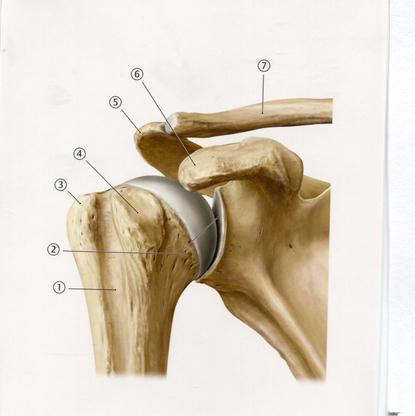

Е. Үлкен бөксе

42. Төменде көрсетілген суреттегі белгіленген №5 анатомиялық құрылымды атаңыз.

47. Төменде көрсетілген суреттегі белгіленген № 7 анатомиялық құрылымды атаңыз.

А. Басының буын беті

В. Латеральды айдаршық

С. Үлкен төмпешік

+D. Хирургиялық мойыны

Е. Шынтақтық шұңқырша

48. Төменде көрсетілген суреттегі белгіленген № 4 анатомиялық құрылымды атаңыз.

А. Акромиальді өсінді